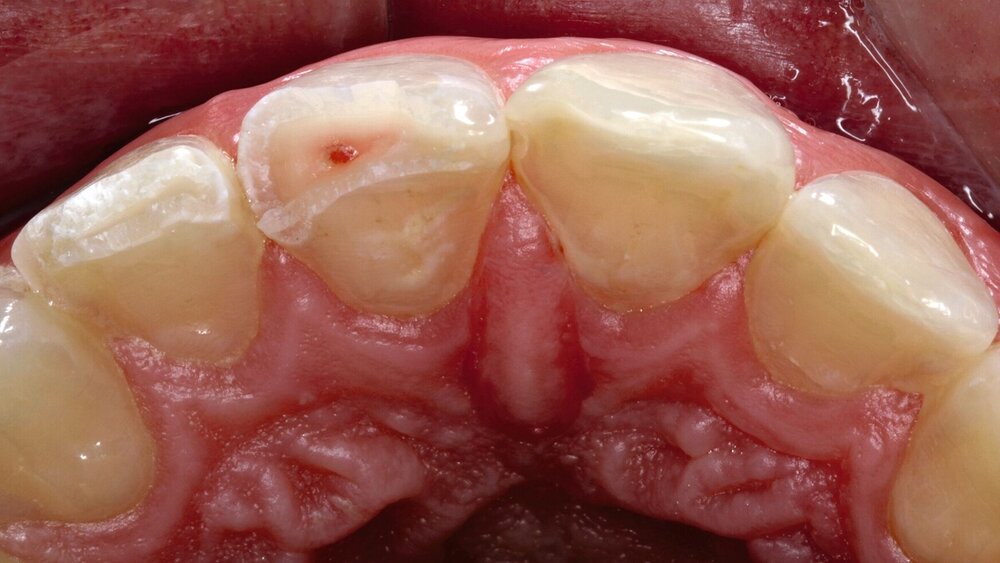

Bei der partiellen Pulpotomie wird zunächst die Kronenpulpa im Bereich der Expositionsstelle um circa 2 mm reduziert [Krastl et al., 2021; Bourguignon et al., 2020]. Dies erfolgt in Lokalanästhesie in einem aseptischen Arbeitsfeld mit einem schnell rotierenden Diamantschleifkörper unter Wasserkühlung (Abbildung 1). Kommt es intraoperativ zu einer anhaltenden Blutung von mehr als fünf Minuten, muss von einem lokal entzündeten Gewebe ausgegangen werden und eine vollständige Pulpotomie, das heißt die Entfernung der gesamten Kronenpulpa, kann in Erwägung gezogen werden.

Abschließend wird sowohl bei der direkten Überkappung als auch bei der (partiellen) Pulpotomie die Pulpawunde mit einem pulpaverträglichen, bioaktiven Material (zum Beispiel hydraulischer Kalziumsilikatzement oder Kalziumhydroxid) abgedeckt und dieses einschließlich der freiliegenden Dentinoberfläche bakteriendicht versiegelt [Widbiller und Galler, 2018].